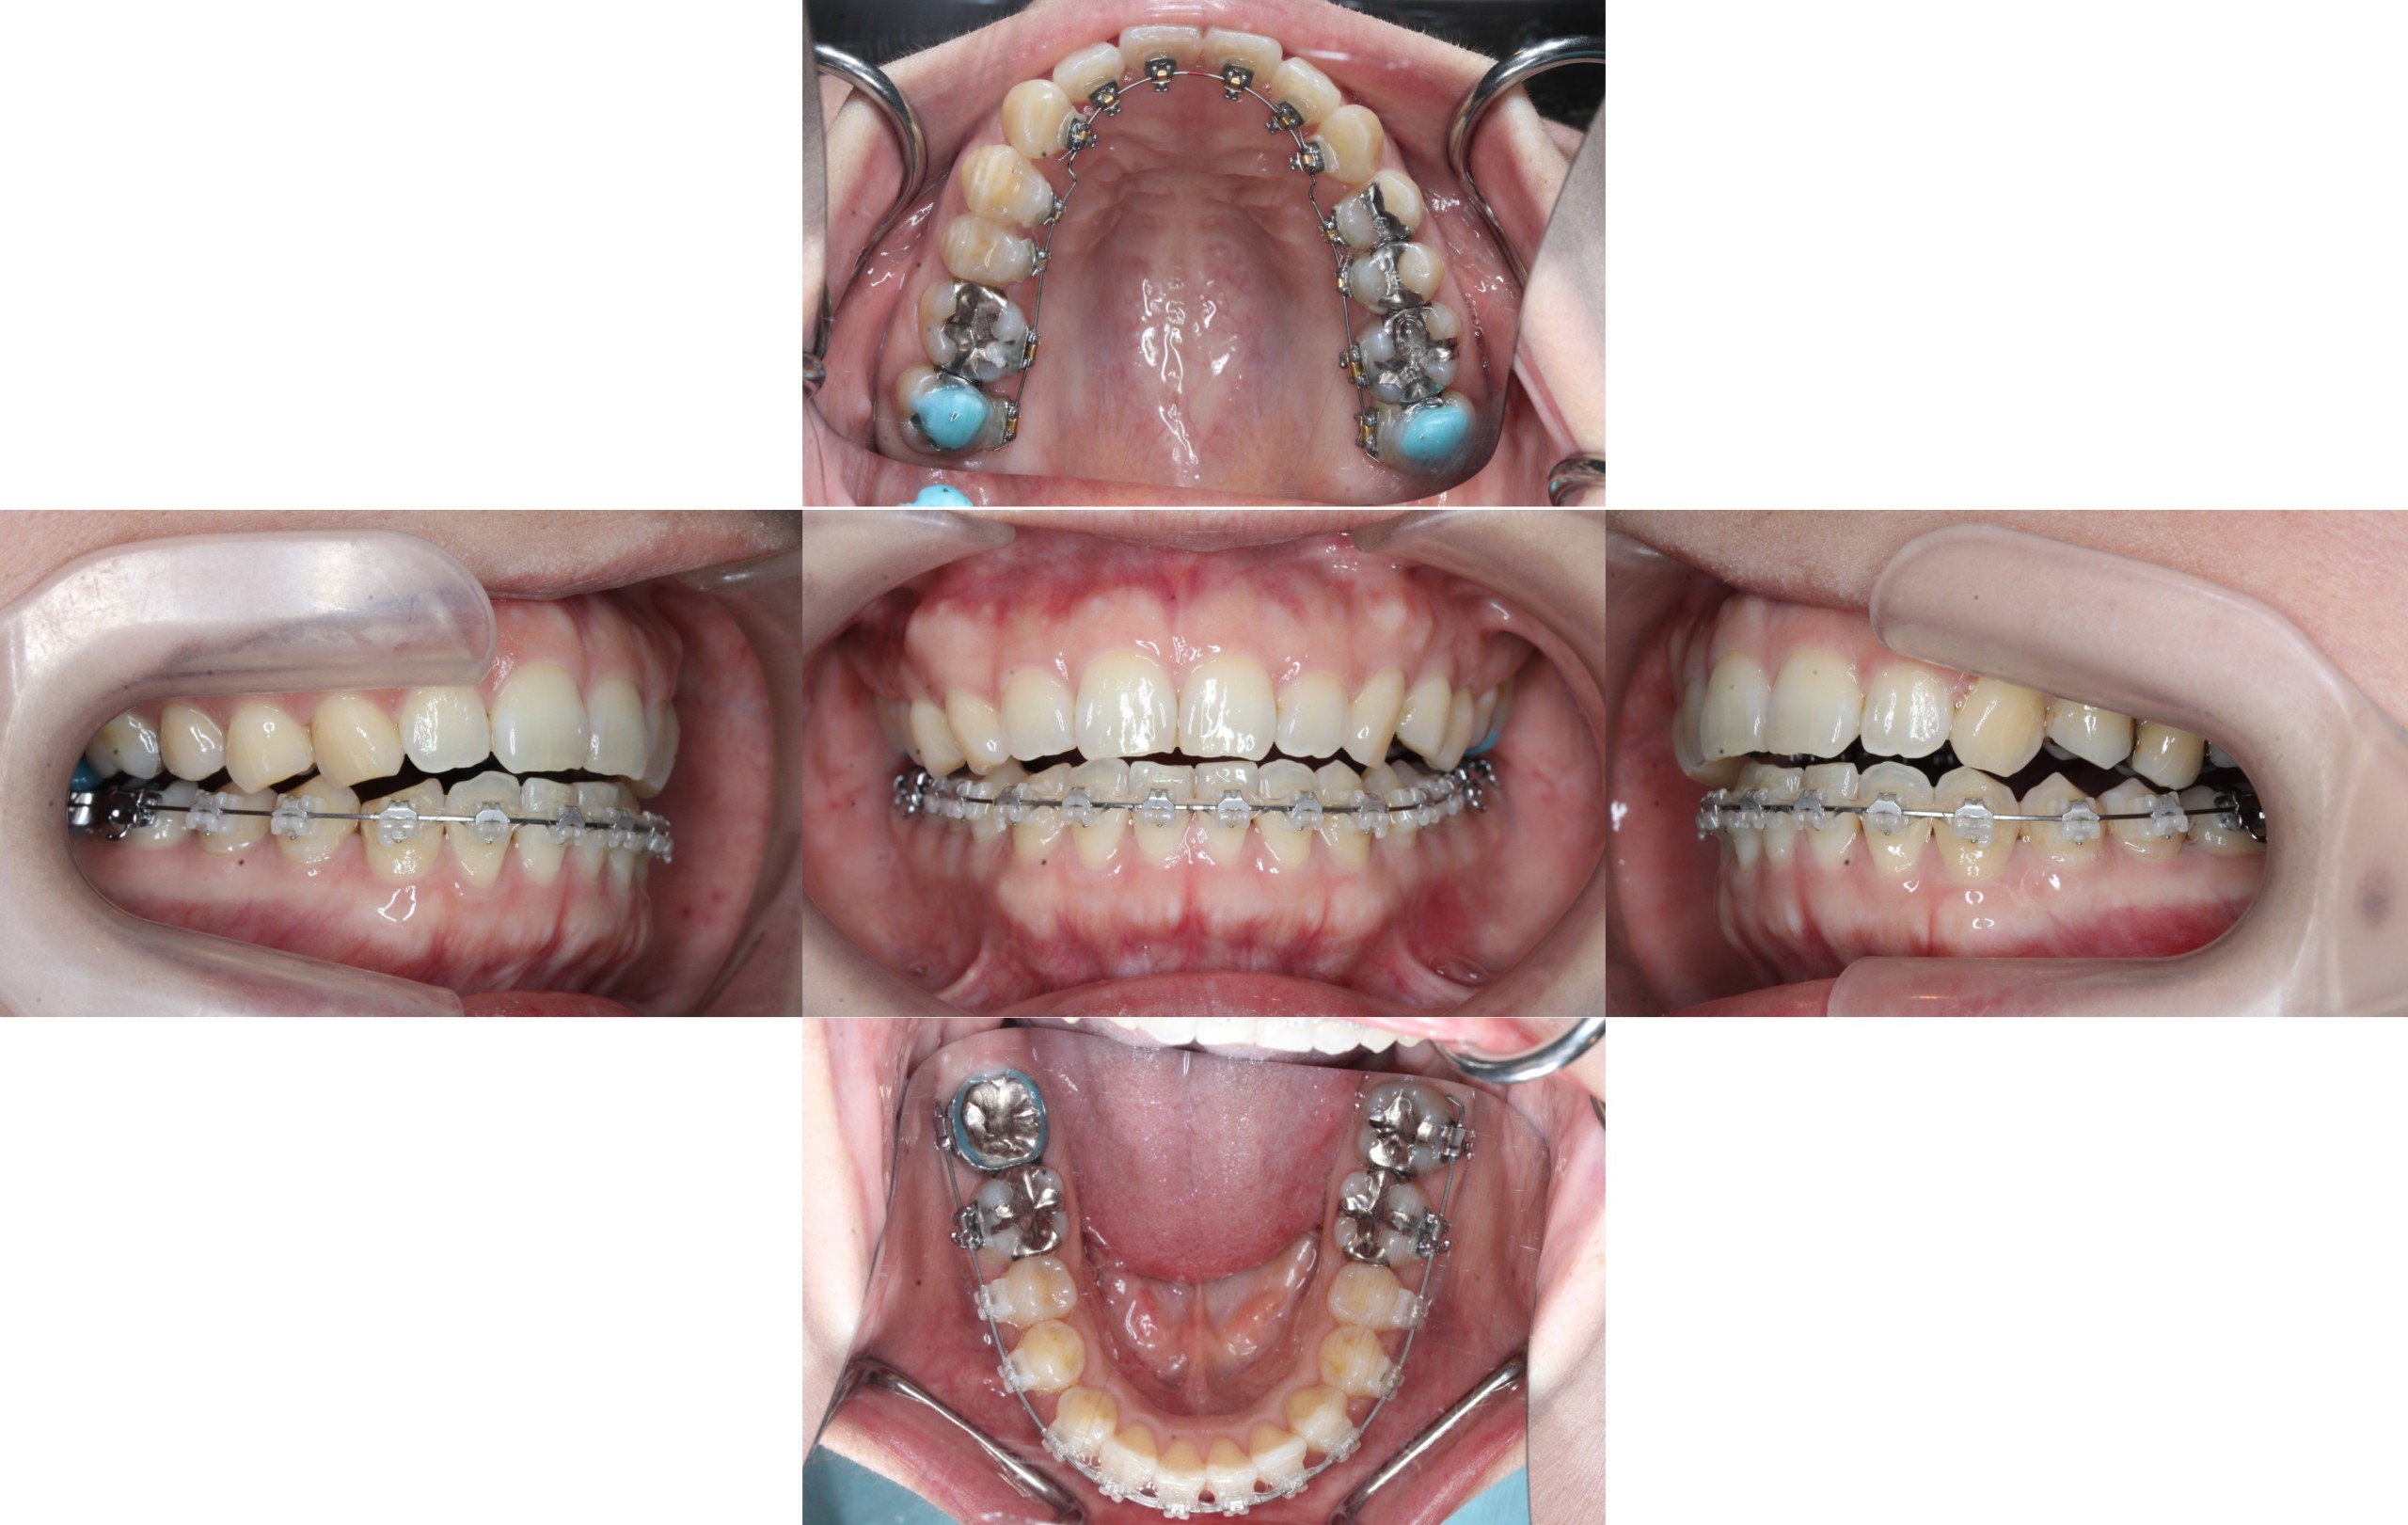

装置装着

約3ヶ月経過